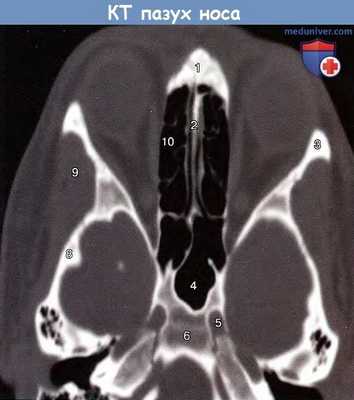

На рисунке ниже представлена компьютерная томография черепа (придаточные пазухи носа). На рентгенограммах, выполненных в различных проекциях, можно видеть свод и основание черепа, кости лица. Контуры свода черепа на рентгенограммах имеют вид двойной линии (более светлой) компактного костного вещества. Более четкая и ровная внешняя линия соответствует наружной пластинке костей свода черепа, а различной толщины внутренняя линия представляет собой внутреннюю пластинку.

Придаточные пазухи носа. Аксиальная проекция (компьютерная томография):

1 — носовая часть лобной кости; 2 — костная перегородка носа;

3 — скуловая кость; 4 — клиновидная пазуха; 5 — сонная артерия; 6 — скат;

7— наружный слуховой проход; 8 — клиновидная кость;

9 — височная мышца; 10 — решетчатые ячейки.